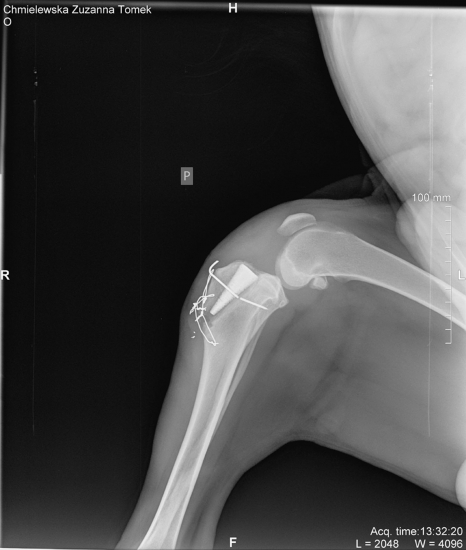

).W ruchu widoczna wyraźna kulawizna prawej kończyny miednicznej. Badanie w sedacji : niestabilność tylno-przednia z objawem uskoku i rotacją podudzia w kierunku bocznym.Rozpoznanie kliniczne - niezupełne zerwanie więzadła krzyżowego przedniego.

Artrotomia przyrzepkowa boczna prawego kolana: zerwany boczny pęczek więzadła krzyżowego przedniego, pęczek boczny rozciągnięty, płaski osteofit wzdłuż bocznego grzebienia bloczka kości udowej. Substytucja więzadła według techniki własnej.Usunięto osteofit. Płukanie stawu.Szwy substytutu i torebki stawowej - amifil -"4/6". Szew powięzi szerokiej i szew powięzi podskórnej - maxon 1/0. Szew skóry Kryty Halsteda - amifil m "1". Opatrunek miękki gruby do pachwiny na 2 tygodnie."